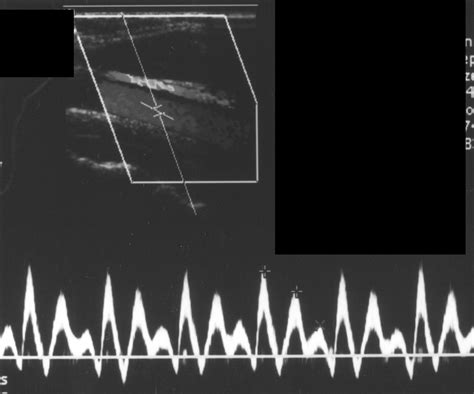

To understand the Atrial Kick, one must first visualize the cardiac cycle. The heart consists of four chambers: two upper chambers called atria and two lower chambers called ventricles. During the filling phase of the heart (diastole), blood flows passively from the atria into the ventricles through open valves. This passive filling accounts for approximately 70% to 80% of the total ventricular volume.

The Atrial Kick represents the final 20% to 30% of blood that is pushed into the ventricles during the late stage of diastole. This occurs when the atria contract—triggered by electrical signals from the sinoatrial (SA) node—forcing the remaining blood through the atrioventricular valves. Although it may seem like a small percentage, this "kick" is vital for maintaining optimal cardiac output, especially during periods of physical exertion or when the heart is already under stress.

• Support During Exercise: When the body demands more oxygen, heart rate increases, leaving less time for passive filling. The Atrial Kick becomes essential to compensate for this shortened filling window.